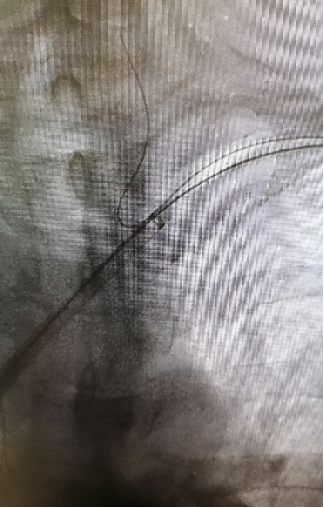

★Case 3 主动脉破裂+右位弓+ 迷走左锁骨下动脉+ Kommerell憩室

治疗难点:主动脉濒临破裂、解剖复杂

手术策略:Castor支架迅速封堵破口+潜望镜技术重建双侧锁骨下动脉

结果:快速稳定血流,患者转危为安

术后一月复查CTA,Castor支架及潜望镜通畅,假腔隔绝良好,纵膈及胸腔血肿吸收。

术后一年复查CTA,潜望镜远端出现Ib型内漏